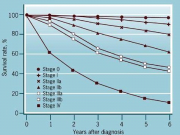

| 07:11, 7 בספטמבר 2012 | Breastgraph312.png (קובץ) |  |

109 קילו־בייטים | Motyk | 1 | |